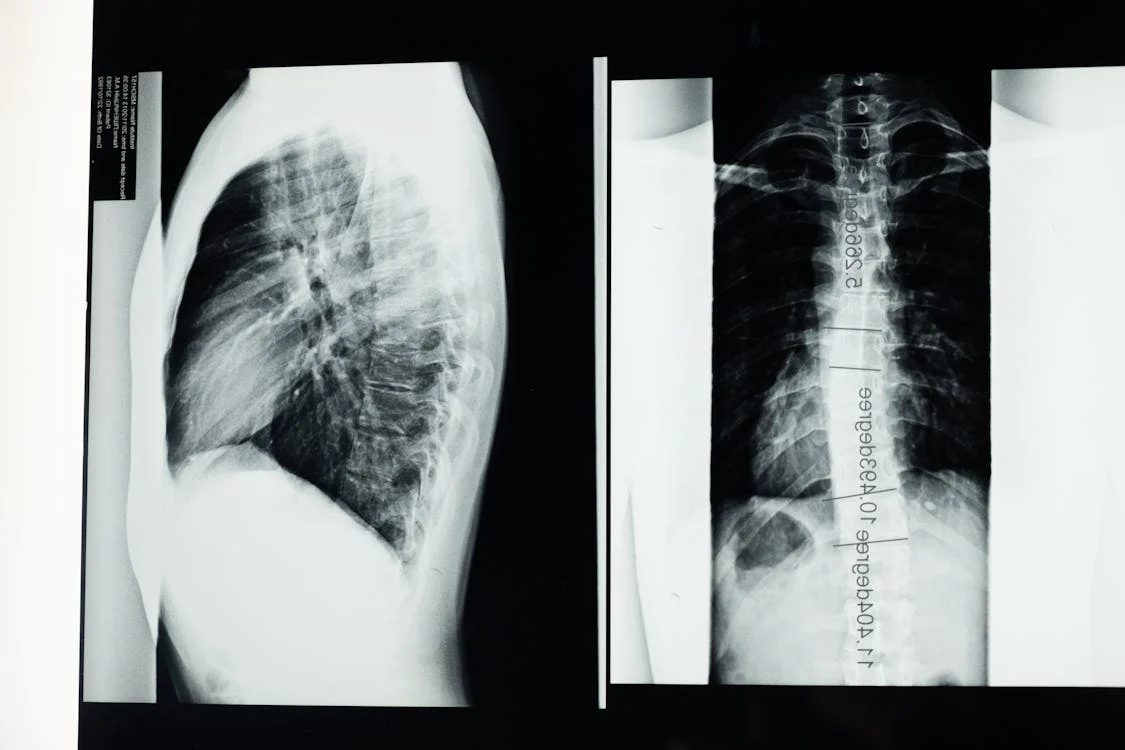

A súlyosabb gerincferdülés esetében a gerinc görbülete olyan mértékű lehet, hogy az a mellkas formáját is befolyásolja. Ez a deformitás a tüdő kapacitásának csökkenéséhez vezethet, ami légzési nehézségeket okozhat. Az érintettek gyakran tapasztalják, hogy nehezebben kapnak levegőt, különösen fizikai megterhelés során.

Ez a probléma nemcsak a tüdőre, hanem a szívre is hatással lehet, hiszen a mellkas deformitása miatt a szívnek is keményebben kell dolgoznia. Ez hosszú távon szívproblémákhoz vezethet, különösen akkor, ha a gerincferdülést nem kezelik megfelelően.